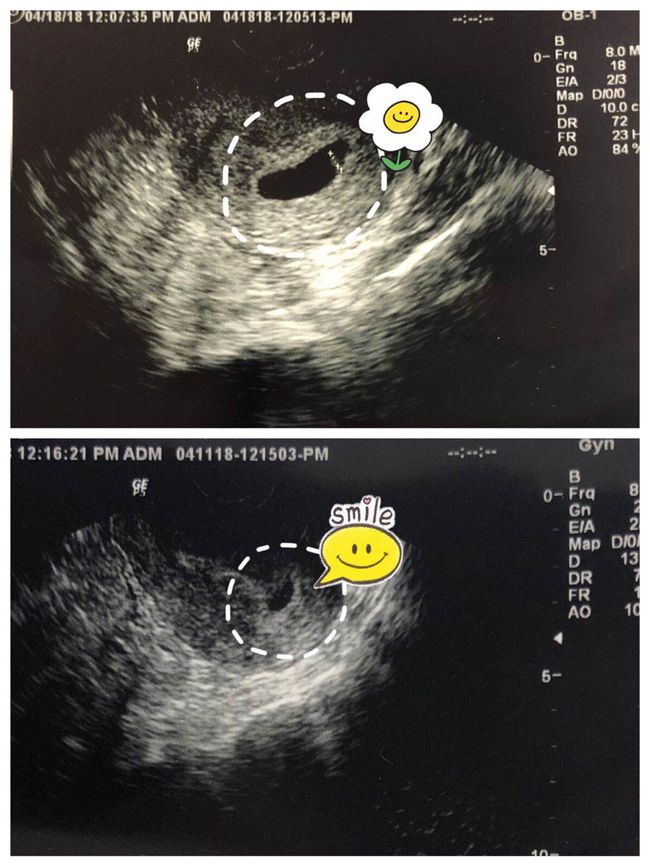

3. 监测卵泡:通过超声监测卵泡的发育情况,确定取卵的最佳时机。

4. 取卵手术:在麻醉下,医生通过超声引导,使用细针穿刺卵巢,吸取卵泡液。